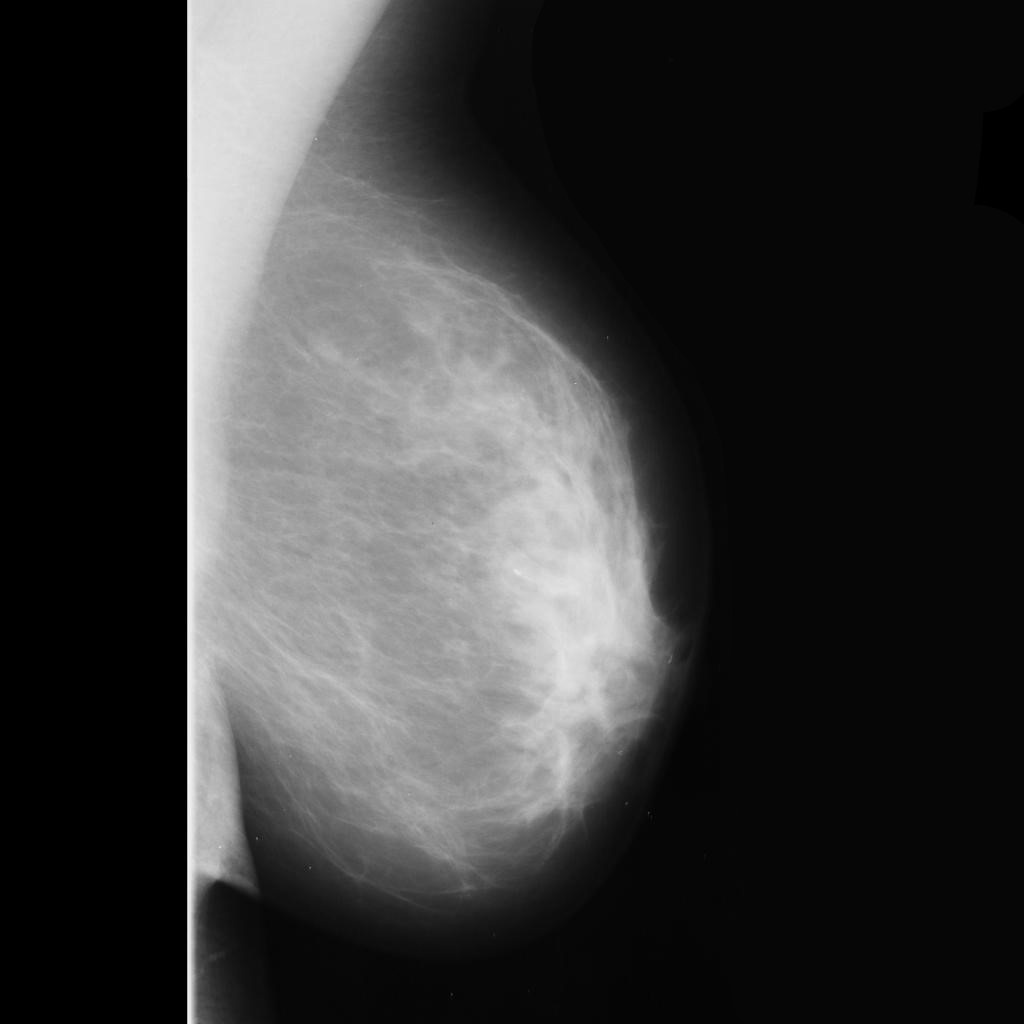

benign